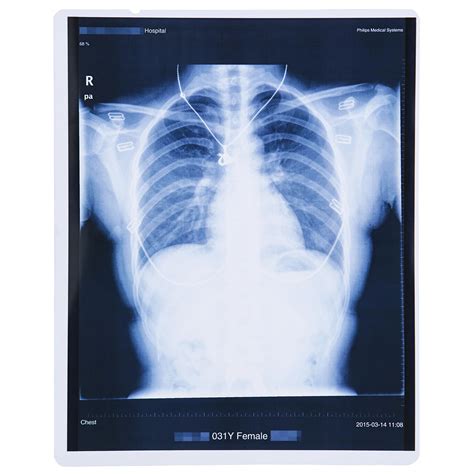

Chest Imaging

Chest X-rays are routinely used to diagnose conditions affecting the lungs, heart, and other thoracic structures. They can detect pneumonia, lung cancer, heart failure, and other respiratory issues. Chest X-rays are often the first line of imaging for patients with respiratory symptoms.